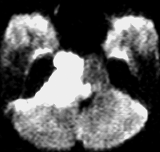

とても若い患者さんで歩行障害などの脳幹部症状は全くありませんでした。第4脳室に発生して脳幹部(橋)背側に食い込んでいる類表皮のう胞です。これを全摘出することは難しく,行えば重い脳幹部症状を出す大きなリスクがあります。

患者さんとよくよく相談して,開頭手術で全摘出しました。

薄いのう胞壁を脳幹内部から確実に摘出するためには,橋の背側の脳組織をほじくり回すような手術になります。

術後は体幹失調で術直後は車椅子になりましたが,リハビリで普通に歩行ができるようになりました。眼球運動障害も回復しています。

安易にお勧めできる手術ではありませんでした。